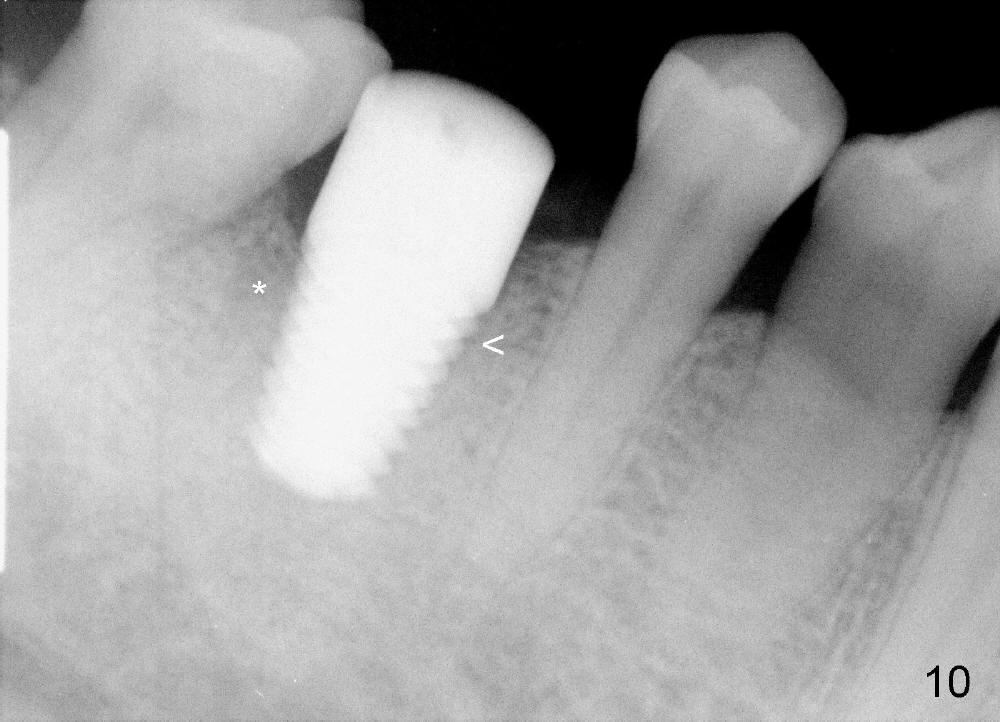

The distal socket is closed completely with suture, whereas the mesiobuccal space is partially closed with collagen gauze and suture (Fig.8 *). The wound is then covered by perio dressing. The gingiva heals around the implant 18 days postop (Fig.9). Three months postop, the implant is stable. The mesial upper portion of the threads appears to have better contact with the bone (Fig.10 <, as compared to Fig.7); the density of the distal socket seems to increase (*). There is no buccal plate atrophy (Fig.11 ^). Supragingival margin is designed for the crown to prevent periimplantitis (Fig.12)

When a large implant is placed in a molar socket, one dimension of the remaining socket is small (buccolingual for lower, mesiodistal for upper). It is apparent that the mandibular buccal and lingual gingiva is relatively loose for the most time, the mesial and distal socket could be closed by suturing and perio dressing. The maxillary palatal gingiva is particularly thick and tough to be approximated. It appears necessary to develop a technique using an immediate provisional to close the socket or place an abutment. Cortex-like bone seems to have grown into the mesial thread spaces 3 years post cementation (Fig.13 <). The 7x17 mm implant was placed buccal (Fig.14 B). The slowly resorbed buccal plate seems to darken the buccal gingiva (Fig.15 B). The bone next to the implant is dense 6 years post cementation (Fig.16 *). The implant at 19 should be smaller and placed lingual.